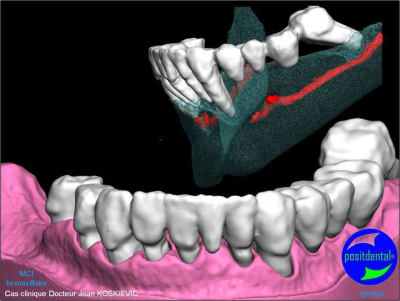

Extractions MCI en 1 chirurgie

gestion des artéfacts en présence de couronnes

chirurgie à venir

3D maxillaire inférieur et photo